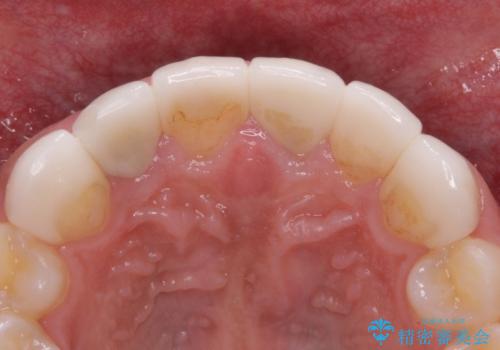

欠けてしまった前歯のセラミック 同じ色合いで再製作

- 前歯のセラミッククラウンが欠けてしまったとのことで来院された患者様です。

周りの他の歯もセラミッククラウンやラミネートベニアが装着されていたため、欠けてしまったクラウンを丁寧に取り外し、同じような色合いとなるように製作することとしました。

欠けたセラミッククラウンを丁寧に外して技工所に送ったことで、元のセラミッククラウン同様の色合いとなり、自然な仕上がりとなりました。